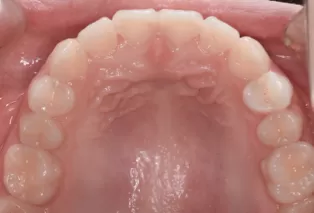

Intraoral photos